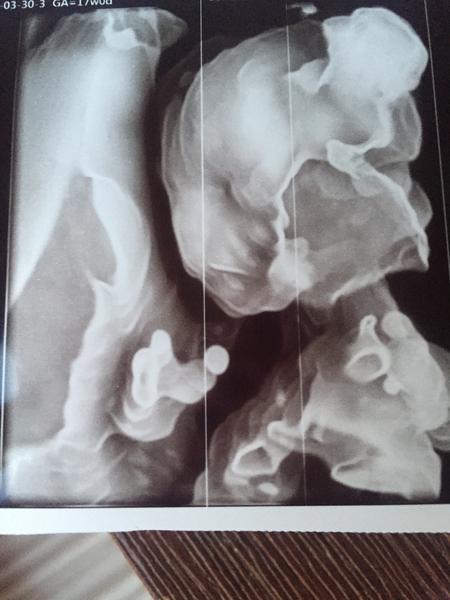

Bambule všetko v poriadku na sone ☺️

Ešte v utorok mám ísť na genetiku ale ja už som spokojná